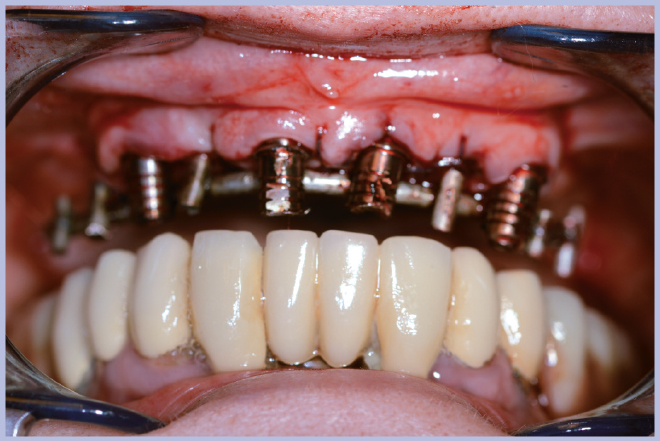

Dopo l’estrazione dei 3 elementi residui (Fig. 2), sono stati posizionati 4 impianti Max Stability Ø3,75 mm (2 di lunghezza 10 mm e 2 di lunghezza 12 mm).

Dopo il posizionamento implantare si sono utilizzati 4 monconi per protesi avvitata angolati a 25°. Dato che non si è utilizzato alcun modello in gesso ma si è lavorato direttamente in bocca, la procedura ottimale in questi casi è quella di rimuovere dai monconi gli esagoni Exacone® 360°.

Sui monconi, dopo aver attivato la connessione a cono Morse (Fig. 3), sono state fissate le apposite cappette in titanio con le viti a testa alta (Fig. 4) ed è stata realizzata un’armatura di rinforzo per mezzo di una sincristallizzatrice intra-orale. In particolare la barra è stata ottenuta mediante saldatura sulle cappette di un filo pre-modellato di titanio grado 2 (Figg. 5, 6).

- Fig. 3 – Posizionamento dei monconi per protesi avvitata

- Fig. 4 – Fissaggio delle cappette in titanio